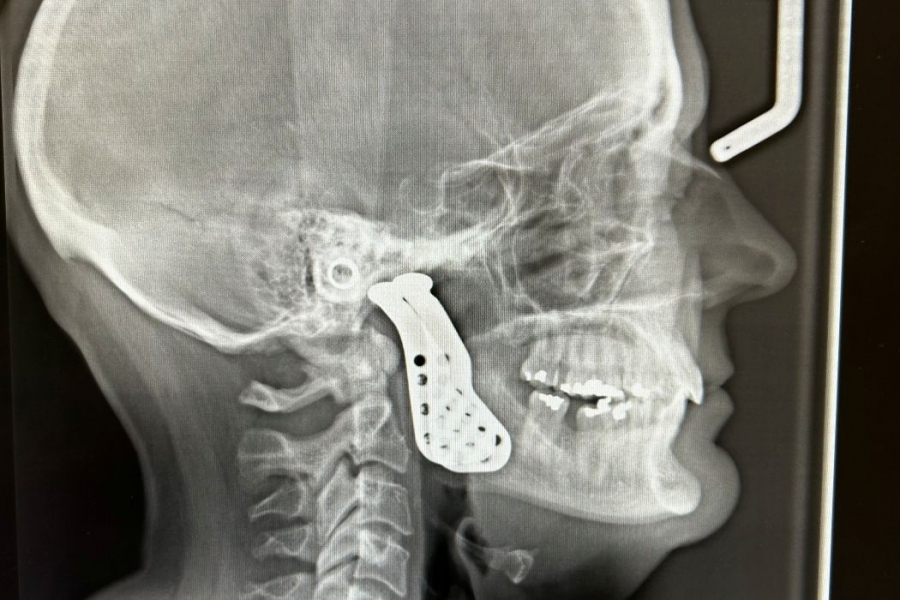

Rady Faculty of Health Sciences UM dental college team conducts Manitoba’s first jaw joint replacement surgery